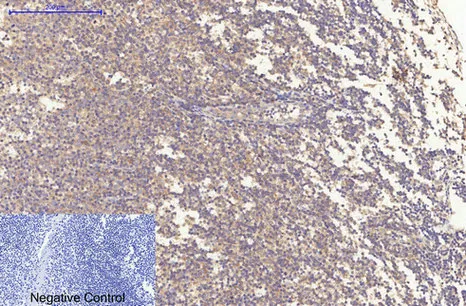

LC3A(5G10)Mouse Monoclonal Antibody

Cat: AMM13240

Size1:50μL Price1:$118

Size2:100μL Price2:$220

Size3:200μL Price3:$380

Application:WB,IF-P,IF-F,ICC/IF,IHC-P

Reactivity:Human,Rat,Mouse

Conjugate:Unconjugated

Optional conjugates: Biotin, FITC (free of charge). See other 26 conjugates.

Gene Name:MAP1LC3A